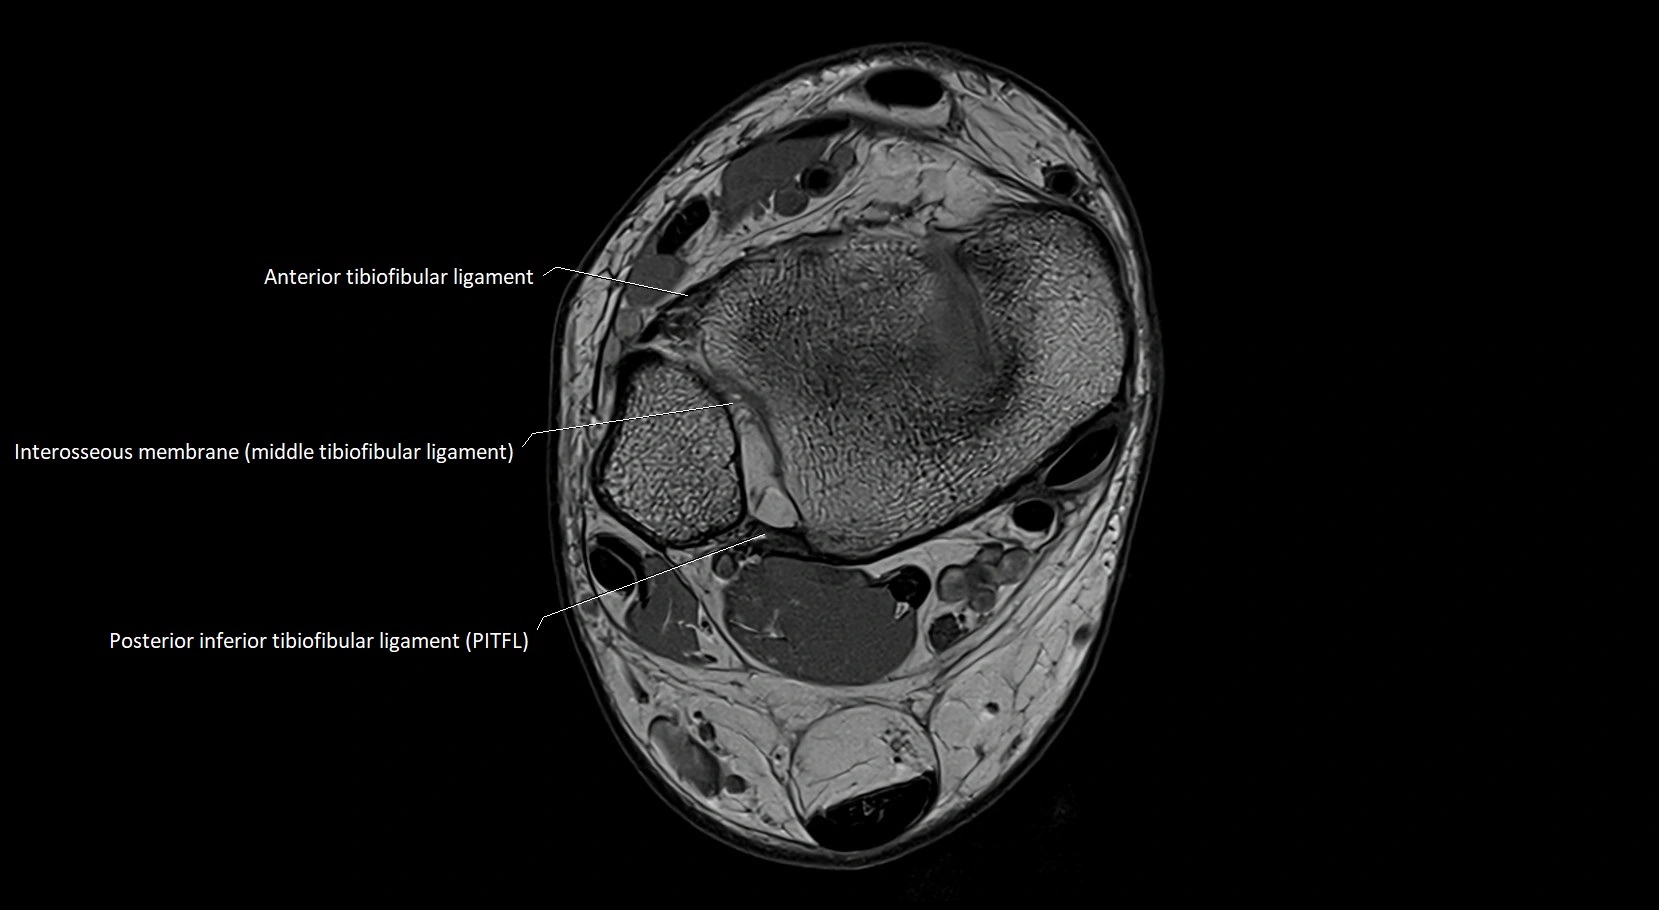

MRI image

image